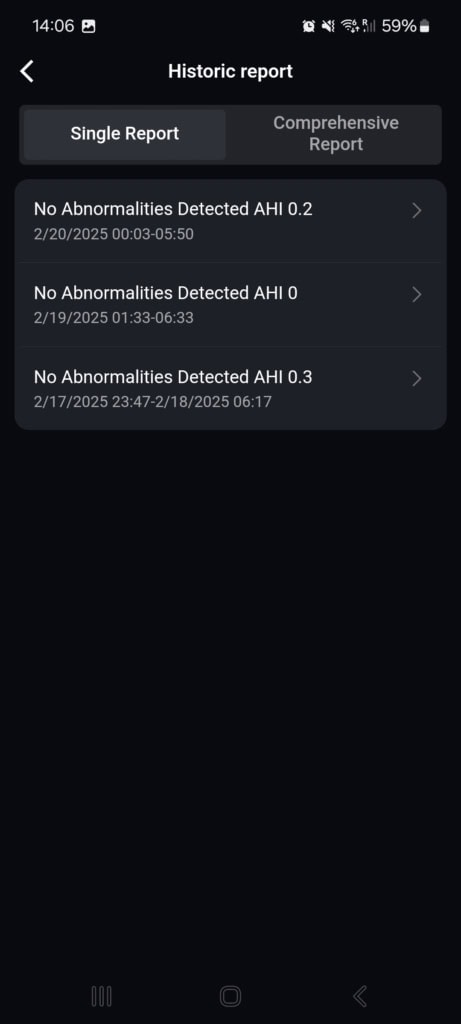

Na podstawie wahań saturacji krwi i tętna w nocy uzyskasz swój wskaźnik bezdechu-hipopnoe (AHI), który oznacza średnią liczbę epizodów z całkowitym zatrzymaniem oddechu i płytkim oddychaniem. Im wyższy wskaźnik, tym poważniejsze może być twoje zaburzenie.

Aby uzyskać kompleksową analizę, smart ring potrzebuje trzech nocy, podczas których wykrywa nieprawidłowości oddechowe. Na podstawie ustalonego wskaźnika dochodzi do zmiany trybu monitorowania. Użytkownicy z niskim lub zerowym wskaźnikiem nie wymagają dalszego monitorowania. Osoby w strefie lekkiego bezdechu mogą zmienić tryb na jedno automatyczne pomiarowanie w celu weryfikacji wyniku. W przypadku wysokiego wskaźnika i podejrzenia średniego do ciężkiego bezdechu dostępne jest codzienne automatyczne monitorowanie.

Po trzech nocach mój wskaźnik wyniósł 0, 0,2 i 0,3 i nie wykryto żadnych nieprawidłowości. Wartość jest bardzo odległa od dolnej granicy lekkiego bezdechu (5,5), więc nie było potrzeby dalszych pomiarów. Ponieważ nie cierpię na obturacyjny bezdech senny, nie pozostaje mi nic innego jak zgodzić się z tą oceną.